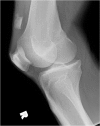

Normal development of the patella typically involves fusion of secondary ossification centers into a single bone during adolescence, with failure of fusion resulting in bipartite and tripartite patellae. In such variants, injury to incomplete ossification center fusion, though uncommon, has been reported to occur in the setting of traumatic quadriceps tendon rupture. The authors present a rare and complex case of traumatic bipartite fragment separation, patellar avulsion, and a complex partial quadriceps tendon tear confirmed surgically in a 36-year-old male. In this case, a tear in the lateral aspect of the quadriceps tendon attached to the nonfused patellar ossification center resulted in retraction of the band containing the bipartite fragment and separation of the patellar fragments, with superior displacement of the smaller bony avulsion likely due to complex attachments from the medial aspect of the quadriceps tendon. Knowledge of the classical locations of a bipartite and tripartite patella can aid in the differentiation of the anatomic variant versus patellar avulsion. Additionally, knowledge of the variable and complex nature of the quadriceps tendon aids in understanding the process of patellar avulsions and various tears, leading to the appropriate orthopedic management.